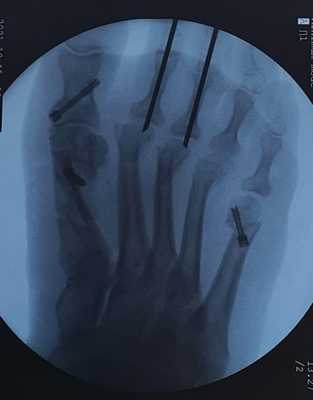

Пациентка А. 57 лет. Тяжёлое поперечное плоскостопие. Молоткообразная деформация 2-3 пальцев. Деформация Тейлора.

Определяется выраженное поперечное распластывание стопы, искривление всех 5 пальцев стопы, выраженная боль под головками 2-3-4 плюсневых костей.

остеотомия скарф 1 плюсневой кости

остеотомия акин основной фаланги 1 пальца

остеотомия вильсон 5 плюсневой кости

остеотомия вейль без фиксации 2-3-4 плюсневых костей

артропластическая резекция проксимальных межфаланговых суставов 2-3 пальцев с фиксацией спицами